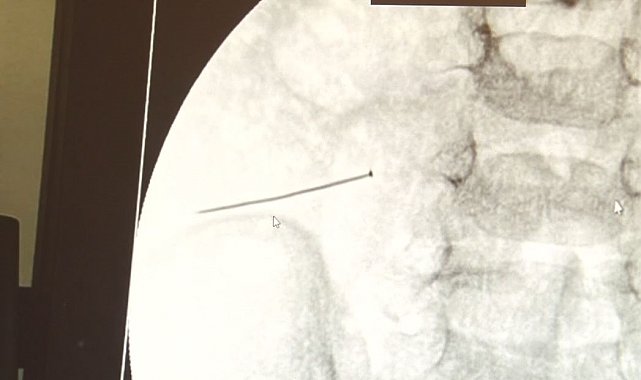

Öte yandan, yaklaşık 3 santimlik toplu iğne filme yansıyan görüntüsüyle gözler önüne serildi.

İstanbul'da 2 yaşındaki çocuk iddiaya göre toplu iğne yuttu sonrasında adeta karın ağrısıyla yerinde duramaz hale geldi. Babaanne, küçük çocuğun şikayetleri üzerine Şehit Prof. Dr. İlhan Varank Sancaktepe Eğitim ve Araştırma Hastanesi'ne götürdü. Burada yapılan tetkiklerde 2 yaşındaki çocuğun ince bağırsağında yaklaşık 3 santimlik toplu iğne olduğu ve bağırsağı deldiği belirlendi. Görüntülemeler sonrası 30 Ekim akşamı Çocuk Cerrahisi Kliniği Eğitim ve İdari Sorumlusu Doç. Dr. Sefa Sağ ve ekibi hemen ameliyata girdi. Başarılı operasyonla iğne olduğu noktadan alınırken aile de rahat bir nefes aldı. Doç. Dr. Sağ ise taburcu edilen hastasının durumuna ilişkin bilgi verirken yabancı cisim yutmalarına karşı ailelere önemli uyarılarda bulundu.

Çocuklarda yabancı cisim yutulmasına yönelik konuşan ve hastasına ilişkin bilgi veren Doç. Dr. Sefa Sağ, "Soluk borusuna kaçması durumunda çocuğun Allah göstermesin ölümüyle veya ömür boyunca yatağa bağımlı kalmasıyla neticelenebilecek sonuçlar doğurabiliyor. Yutulması durumunda da gastrointestinal sistemin herhangi bir yerine takılmadığı müddetçe ekseriyâ yabancı cisimlerin dışarıya çıkmasını bekliyoruz. Yabancı cisim yutulmasını 2 grupta inceleyebiliriz. Sıvı ve katı cisimler olarak sıvı; evde kullanılan kimyasal temizlik malzemelerinin yutulması çok ciddi problemler oluşturabilmekte. Ağızda, yemek borusunda ve midede yanıklar meydana getirebilmekte. Uzun dönemde çocukların hayat kalitesini oldukça etkileyen sonuçlar doğurabilmekte. Katı cisimlerden de ekseriyâ kendiliğinden çıkmasını bekleriz ancak böyle delici, kesici aletlerin yutulmasında ise herhangi bir bağırsağın veya gastrointestinal sistemin bir parçasında delinmeler meydana getirebiliyor. Bu çocuğumuzda da aynen böyle bir hadise meydana gelmişti. Sanırım 1 gün önce ailenin yuttuğunu tahmin ettiği bir yabancı cisim; toplu iğne. Ertesi gün bağırsakta delinmeyle sonuçlanmış ve çocukta da ciddi semptomlar meydana getirmişti. Bu şekilde hasta bize başvurdu. Tetkikler sonucunda yabancı cismi tespit ettik, semptomları ve bulgularına göre de çocuğu ameliyata aldık. Yaklaşık 3 santim boyunda bir toplu iğnenin ince bağırsağı deldiğini, ince bağırsaktaki içeriğin de karın içerisine dolduğunu gördük. Ameliyatı başarılı bir şekilde tamamladık, yaklaşık 1 saat süren bir ameliyattı" dedi.